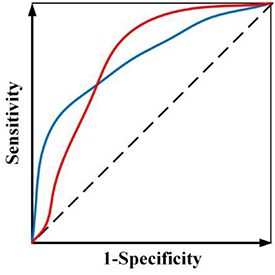

While radiomics has shown promise in various applications, current radiomics approaches face several challenges. First, most radiomics-based approaches combine the features from multiple modalities by simply concatenating them into a long vector to achieve fusion. However, different imaging modalities measure different intrinsic characteristics of a lesion. For example, FDG-PET scanning measures glucose metabolism, while CT scanning provides attenuation coefficient information to x-rays. A simple combination of the features extracted from these different modalities may not yield an optimal predictive model. Second, current radiomics methods often adopt a single objective function (e.g. overall accuracy or area under the receiver operating characteristic (ROC) curve or (AUC)), which may lead to ambiguity when building the predictive model, especially when positive and negative cases are imbalanced. For example, assume there is a radiomics model trained by maximizing AUC and figure 1 shows ROC curves of two candidate models. Although both models have the same AUC value, the ROC curves are different. In clinical applications, one curve would be preferred over the other depending on clinical needs. However, a preferred model cannot be obtained when training through a single objective. Third, a single classifier is typically used in constructing a radiomics model. However, many different types of classifiers are available, and a 'preferred' classifier is often application- or problem-specific and strongly depends on training/testing data (Parmar et al 2015).

Figure 1. Two ROC curves with the same AUC value.

(2) Instead of using AUC as a single objective, a multi-objective model is developed to avoid the ambiguity of maximizing AUC (figure 1). By explicitly considering sensitivity and specificity as objective functions during the model training, a preferred model with emphasis on sensitivity or specificity can be trained according to different clinical needs in the multi-objective model (Zhou et al 2019b). Furthermore, to obtain more reliable results, we designed a new probability-based objective functions to avoid the need of setting a probability threshold in classifying a prediction as positive or negative for the calculation of both sensitivity and specificity.